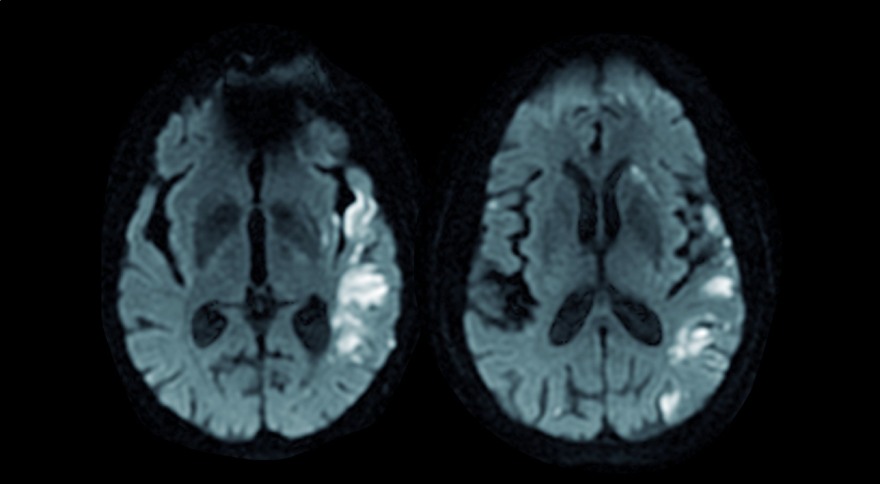

En blanco áreas de isquemia en paciente con tromboembolismos

Aunque no lo parezca a primera vista, algunas patologías cardiacas pueden ser el origen de trombos que al circular por el torrente sanguíneo y llegar a los vasos más estrechos del cerebro generen ictus. "La causa más frecuente de trombos intracardiacos es la fibrilación auricular. Esta patología produce una contracción auricular rápida e irregular que hace que la sangre circule más lenta y con un flujo turbulento, lo que facilita la formación de trombos", explica el Dr. Tomas Datino

, jefe de la Unidad de Arritmias del Hospital Universitario Quirónsalud Madrid y uno de los directores de las VI Jornadas de avances diagnóstico-terapéuticos en fibrilación auricular, que se van a celebrar en el Hospital Universitario Quirónsalud Madrid el próximo 16 de febrero. "Los trombos generalmente se forman en una parte de la aurícula izquierda denominada orejuela. Para prevenir la aparición de trombos puede ser necesario el uso de anticoagulantes; sin embargo, una alternativa a la anticoagulación (sobre todo en pacientes que no pueden recibir esta terapia) es la implantación de un dispositivo que ocluya la orejuela, previniendo la formación de coágulos derivados de la fibrilación auricular sin necesidad de someter al paciente a una terapia anticoagulante".

"El corazón o los vasos enfermos pueden generar trombos que migran al cerebro y que pueden producir falta de riego en distintas partes del cerebro. Estos trombos pueden producir infartos cerebrales, pero también si son muy extensas y repetitivas pueden generar un tipo de demencia", detalla el Dr. Datino que recomienda fervientemente evitar los factores de riesgo cardiovascular, como tabaquismo, colesterol elevado, hipertensión arterial, diabetes mellitus… "Si evitamos o prevenimos estos factores, reducimos mucho el riesgo de las patologías cardiacas y cerebrales".